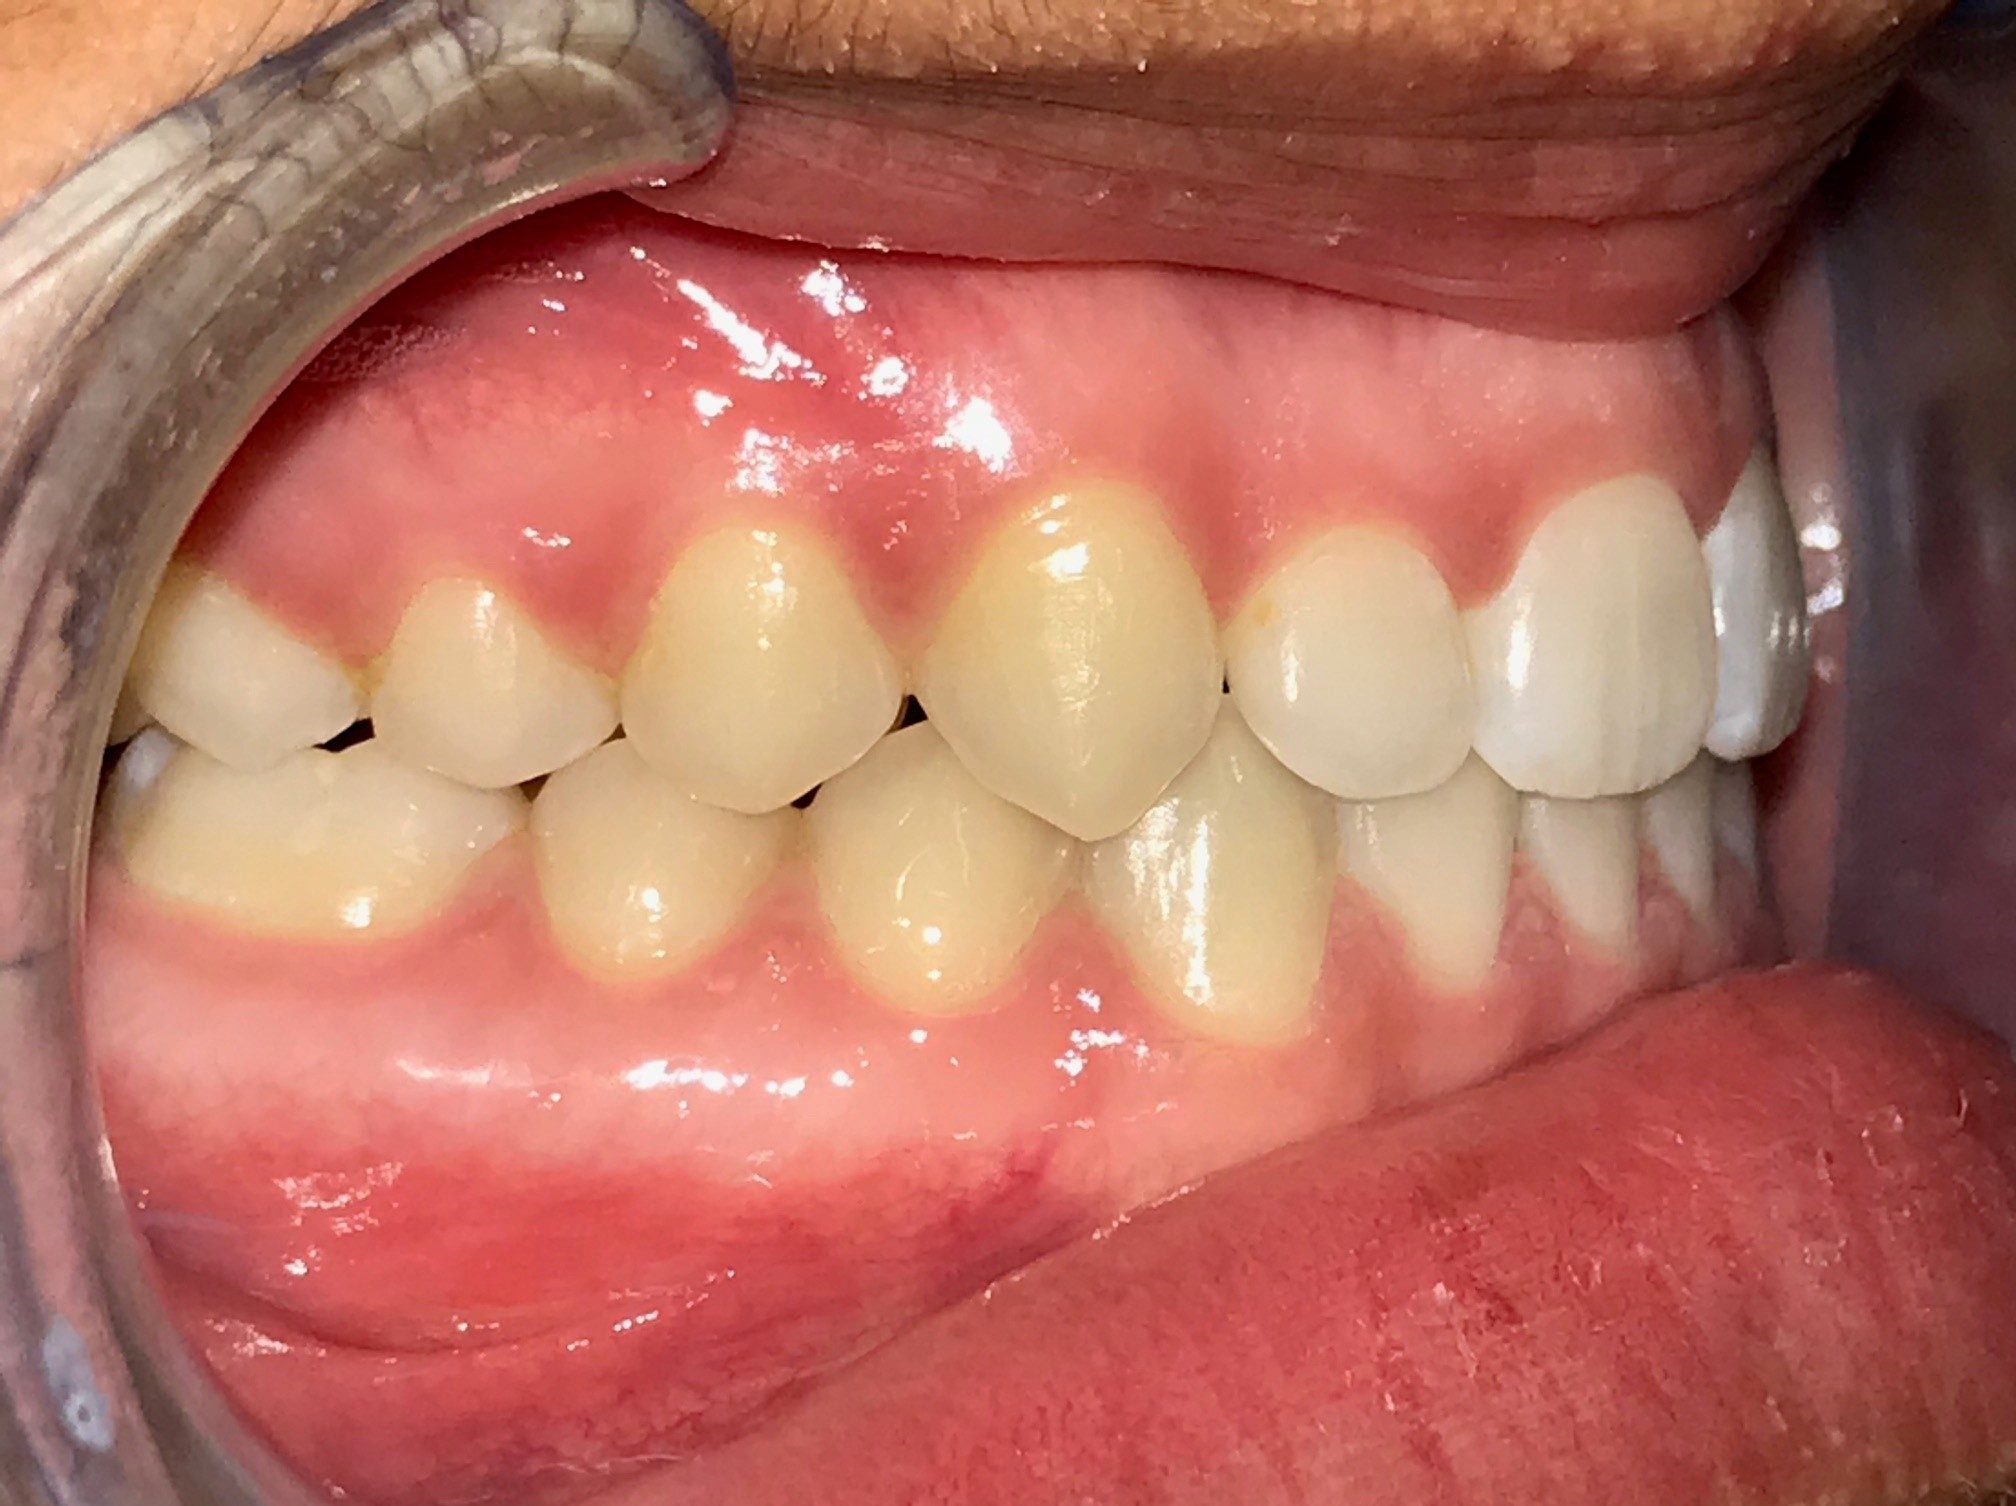

La chirurgie orthognatique (ou chirurgie correctrice des mâchoires) est indiquée lorsqu’il existe un défaut d’alignement entre la mâchoire du haut (maxillaire supérieur) et la mâchoire du bas (mandibule). Ce défaut d’alignement est nommé malocclusion dento-squelettique.

Le manque d’équilibre entre les deux mâchoires peut entraîner des difficultés à mastiquer, des problèmes d’élocution ou de respiration (apnée du sommeil), des douleurs aux dents, à l’articulation de la mâchoire ou aux muscles de la mastication, ainsi que des défauts esthétiques.

Ce manque d’alignement peut se traduire par des mâchoires trop avancées, reculées ou trop étroites l’une par rapport à l’autre, par un excès de gencive visible au sourire, une difficulté à fermer les lèvres, par un menton fuyant ou trop prononcé ou par une asymétrie au niveau du visage.